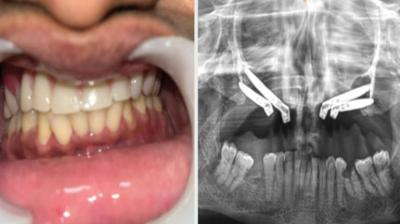

24 वर्षीय युवती के चेहरे पर लौटी मुस्कान और आत्मविश्वास

एम्म में जटिल सर्जरी को सफलतापूर्वक अंजाम दिया है। इस सर्जरी में ट्यूमर के कारण काटे गए निचले जबड़े को पैर की हड्डी से दोबारा बनाया गया और उसमें 13...